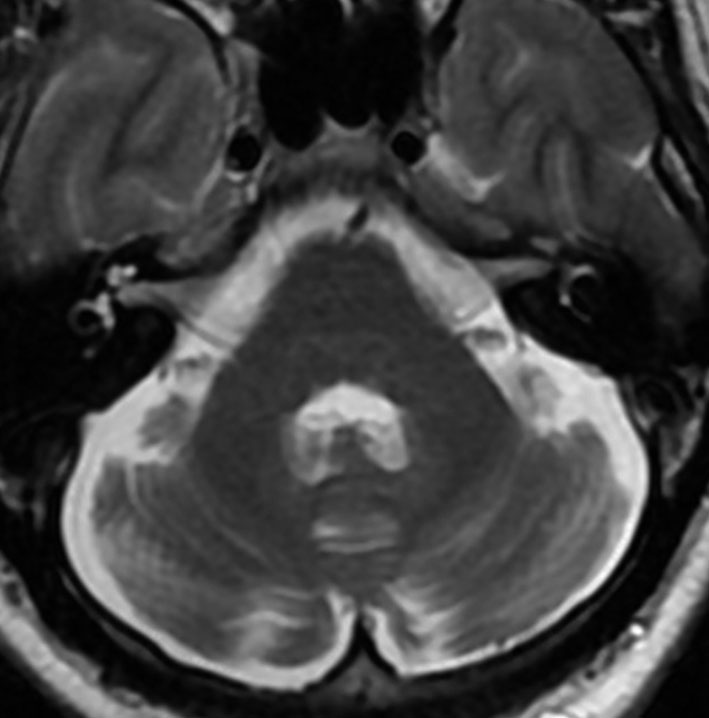

アレビアチン(フェニトイン)やデパケン(バルプロ酸)を何年も服用していると小脳に萎縮がくることがあります。小脳失調症というふらつきがでることは少ないのですが,MRIで小脳が小さくなったようにみえます。

20年以上バルプロ酸の服用をしている患者さんです。左と中央のMRIでは小脳萎縮がありますが,右側の大脳では萎縮は全くありません。小脳症状はありません。